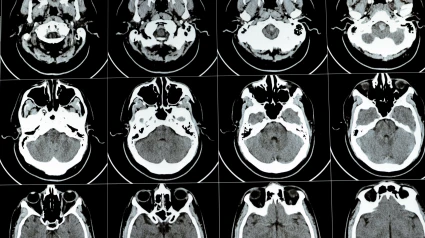

Imagen de recurso